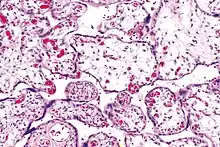

Micrograph of villous immaturity. H&E stain.

Placental villous immaturity is chorionic villous development that is inappropriate for the gestational age.

Immature chorionic villi are larger and have more central blood vessels; thus, the diffusion distance for gas and nutrient exchange is larger and, therefore, placental function is impaired.